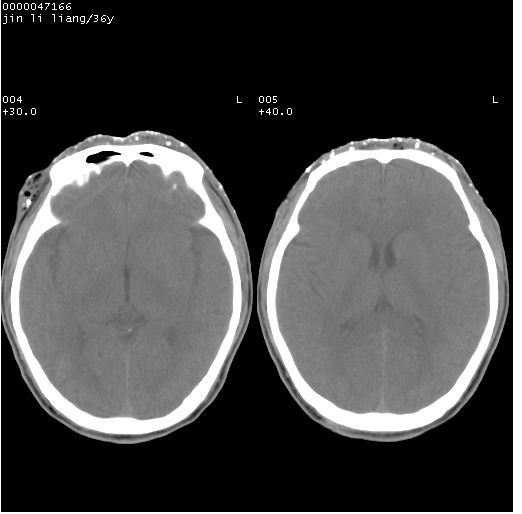

左眼球破裂,异物.

左眼球破裂,球内异物

左眼球内容物浑浊其内见气体影,头面部异物.

左眼球破裂并异物,眶周、额顶部头皮及软组织挫伤并异物

左眼球破裂积气并异物,眶周、额顶部头皮及软组织挫伤并异物!

迎面一炮,满脸开曝。额顶部头皮及软组织挫伤并异物,左眼球破裂积气并异物,典型的面目全非,惨不忍睹。

左侧眼球破裂积气异物存留   颜面额部多处软组织挫伤并异物!

左眼球破裂积气并异物,眶周、额顶部头皮及软组织挫伤并异物,右侧眼环前内分异物

额顶部头皮及软组织挫伤并异物,左眼球破裂积气并异物。可怜

1左侧眼球破裂并积气,球内、框内异物。

2额部顶部软组织伤。